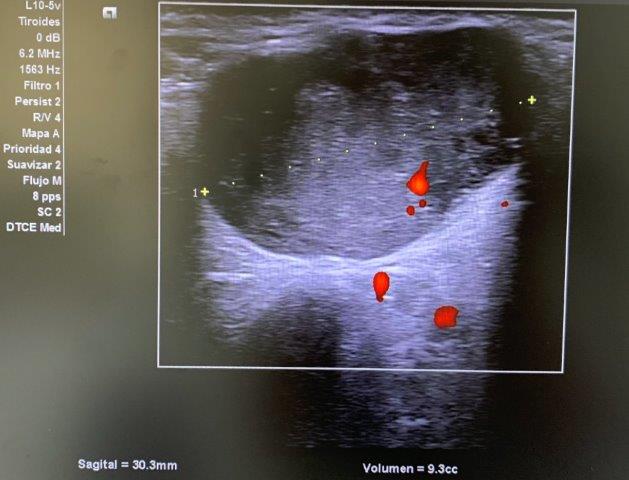

ECO POCUS: imagen isoecoica, heterogénea, redondeada con captación periférica de Doppler, que mide 26.9 x 21.7 mm (corte transversal) y 30.3 mm (corte longitudinal). Vemos un bultoma originado en la cola de glándula parótida.